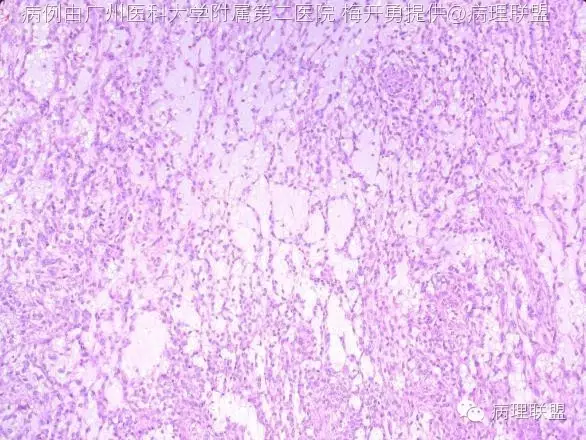

肿瘤位于支气管黏膜下,瘤细胞呈短梭形细胞、卵圆形细胞、多边形细胞和星状细胞,弥漫排列或呈条索状排列,间质呈黏液样。瘤细胞显示有一定的异型性,可见核分裂。形态学类似肌上皮肿瘤或骨外粘液性软骨肉瘤。